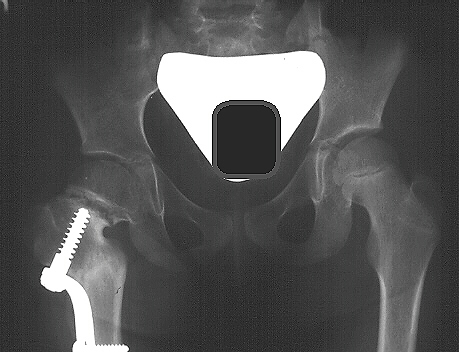

- currently, the most effective surgical treatment is a valgus producing

proximal femoral osteotomy (subtrochanteric vs intertrochanteric procedures

have similar results)

proper surgical treatment also includes:

- adductor tenotomy which allows for less forceful correction and improved

stability

- proximal femoral shortening osteotomy if necessary to help relieve

excessive femoral head pressure when the valgus angle is restored

- stable internal fixation and hip spica cast if needed

- goal of surgical treatment is to produce an overcorrection of valgus

angle to greater than 150 - 160 degrees, as well as, correction of epiphyseal

angle to less than 30 degrees